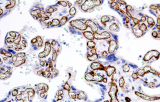

- Assegnazione del lignaggio & principali diagnosi differenziali: Fenotipizzazione cellule B vs cellule T (es. CD20 vs CD3), supportata da fattori di trascrizione nucleari delle cellule B come PAX5 quando i marcatori pan-B sono deboli/assenti.